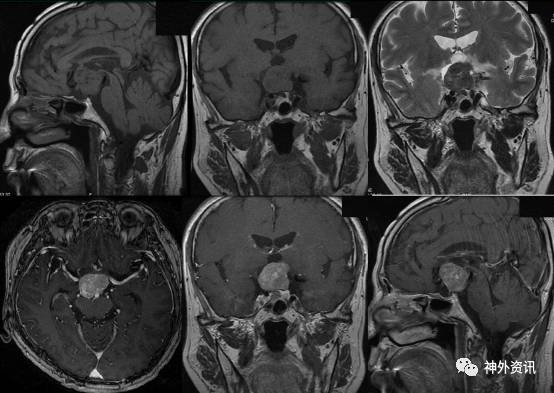

进一步行垂体MR扫描,显示“鞍上一结节状异常信号灶,呈等T1等T2,增强后明显均匀强化,与垂体柄分界不清,视交叉略受压,三脑室底部略受压。垂体变扁呈弧形状紧贴鞍底,增强后均匀强化。考虑鞍上偏后方富血供肿瘤。鞍上占位,脑膜瘤可能性大(图2)”。

图2. 垂体 MRI 检查示:鞍上一结节状异常信号灶,呈等 T1 等 T2,增强后明显均匀强化,考虑鞍上偏后方富血供肿瘤,脑膜瘤可能大。

术后患者一般情况良好,意识清,无尿崩。复查头颅MRI示鞍上肿瘤部分残留,余无殊(图3)。至术后6天,患者出现精神症状,表现为烦躁,电解质、尿量、体温基本平稳,对症处理后恢复良好,于术后13天顺利出院。

图3. 术后MRI检查,提示肿瘤部分残留。